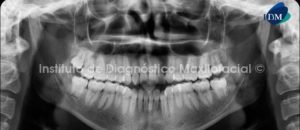

Paciente de 33 años de edad de sexo masculino, es referido al Instituto de Diagnóstico Maxilofacial para evaluar la presencia de una lesión en el lado izquierdo del maxilar superior.